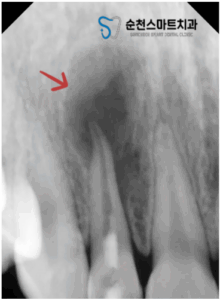

오늘 소개해 드릴분은 10대 여성분으로

오른쪽 작은 앞니가 아프고

뿌리 끝 부분의 잇몸에 염증이 생겨

빨리 치료받고 싶다고 호소하시며 내원하셨습니다.

처음 내원하셨을 때,

불편한 치아의 상태를 정확하게 확인하고자

치근단 방사선사진(periapical)을 촬영한 모습입니다.

우측 작은 앞니 뿌리 끝이

검게 된 것을 볼 수 있는데요.

염증으로 인해,

잇몸에 고름과 치조골 흡수가

일부 된 것을 알 수 있습니다.